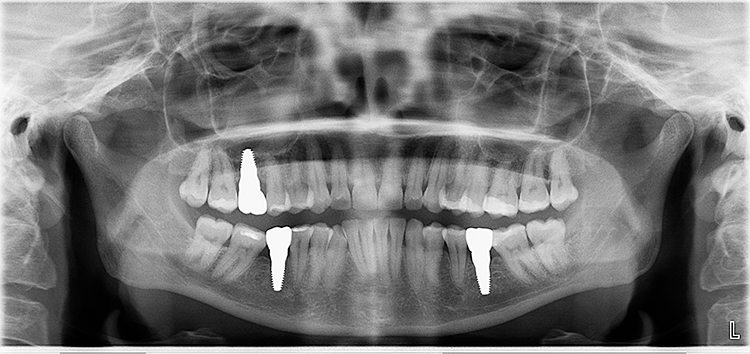

Abb. 2: Repräsentativer Fall von ABH Grad B Septus Typ II. a) Ansichten vor der Installation. Röntgenaufnahme der periapikalen Läsion an einem wurzelkanalbehandelten Molaren und klinische Ansicht der Typ-II-Socket nach der Extraktion. b) Die Ansichten nach der Installation zeigen das Implantat innerhalb des interradikulären Septums und das über dem Implantat platzierte A-PRF. c) Nachuntersuchungen nach 10 Tagen bzw. 2,1 Monaten. Die Röntgenaufnahme zeigt die Knochenbildung zwischen der Sinusmembran und dem apikalen Teil des Implantats. d) Jüngste Nachuntersuchung nach Einsetzen der Prothese.

Abb. 3: Repräsentativer Fall von Grad A Typ I. a) Präoperative Ansicht. Röntgenbild der periapikalen Läsion an einem wurzelkanalbehandelten Molaren. Die Höhe des Alveolarknochens zeigt Grad A an. b) Klinische und radiographische Ansicht der Implantatinsertion unter Verwendung einer Einheilscheibe mit großem Durchmesser (6×8 mm). A-PRF wurde um das Implantat und unter der Scheibe platziert. c) Nachuntersuchung nach 5,9 Monaten vor und nach der Zementierung und Aufbereitung. d) Jüngste Nachuntersuchung nach Einsetzen der Prothese

Abb. 4: Repräsentativer Fall von Grad A Typ III. a) Ansichten vor der Implantation. Röntgenbild der periapikalen Läsion an einem wurzelkanalbehandelten Molaren. b) Die Extraktionsalveole zeigt ein interradikuläres Septum vom Typ III (B).